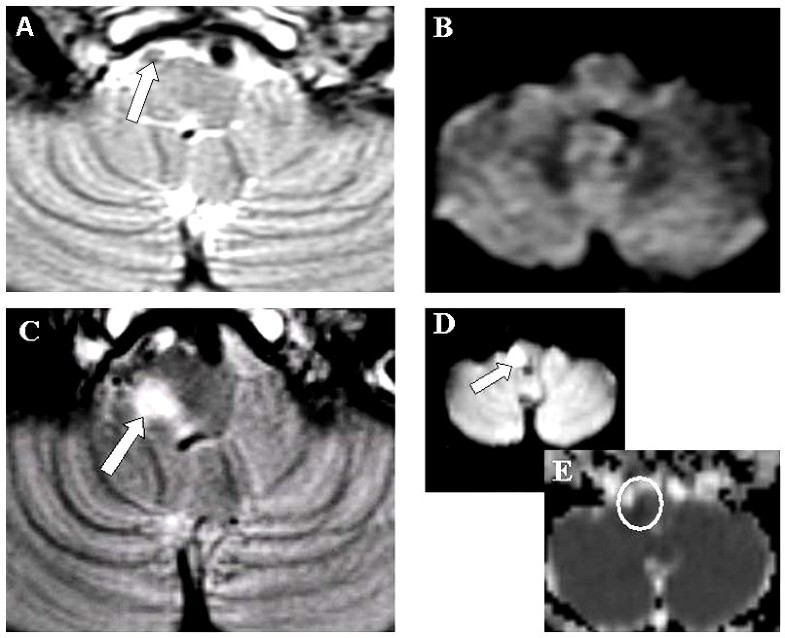

Diffusionnegative MRI in acute ischemic stroke a case report Cases Diffuser Negative Effects Try a patch test before using an essential oil topically. Headaches are also a possible side. Diffusing natural oils can exacerbate asthmatic symptoms, so get medical expertise before doing this. Aromatherapy diffuser side effects | deep aromatherapy. Essential oil diffusers have quickly replaced candles in many households, but are they safe? Aromatherapy diffusers have become increasingly popular in recent years,. Diffuser Negative Effects.